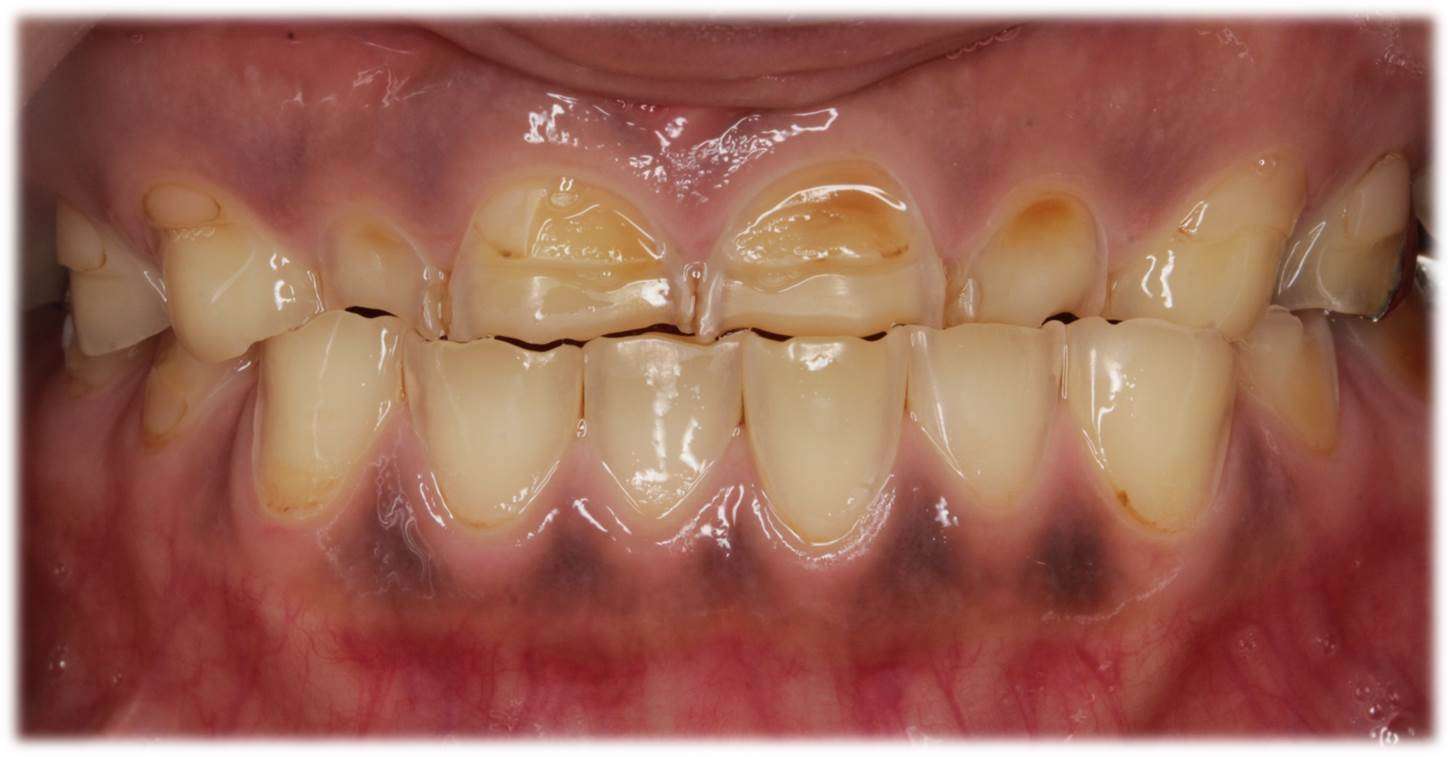

写真画像は,長期に渡り歯が酸に曝露された患者様のお口の様子です。もし,「歯が小さくなってきたかな?」,「歯が削れてきてしみるようになってきたかな?」などの症状でお困りの際には,是非,グランツ歯科クリニックまでご相談ください。補綴専門医・IPSG咬合認定医が相談に乗ります。